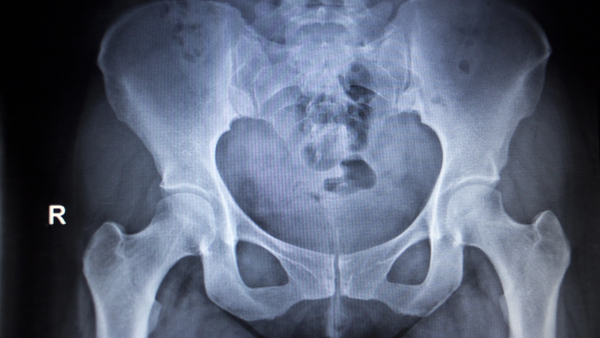

Pain and other symptoms related to the hip and thigh can be caused by various conditions. Issues in this area include hip osteoarthritis, muscle strains, and tendonitis, among others. Here, you can read more about different diagnoses, gain insight into their causes, and learn what can be done to alleviate and manage these issues.